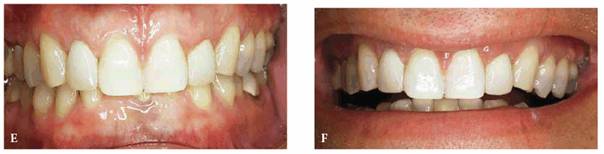

PROBLEM: This 21-year-old male model hesitated to smile because of his

diastemas (see Figures 23-14A, 23-14G, and 23-14I). The patient was also concerned about the appearance

of his inflamed gingiva adjacent to the left central incisor; subsequent

examination showed an overextension of composite bonding. A main requirement of

this patient was immediate esthetic treatment since he was leaving for Italy in

1 week. A second requirement was that no additional tooth be reduced, including

the opposing teeth.

Figure 23-14A: This 21-year-old male model performed both runway and photography modeling without smiling because he disliked the spaces in his teeth.

TREATMENT: To maximize longevity and esthetics, porcelain laminates were

chosen as the most conservative treatment. Figure 23-14B shows the previously bonded left central

incisor coated with dentin-disclosing solution to determine how much enamel was

left. The tooth is washed, leaving red dye to indicate dentin areas (see Figure 23-14C). Figure 23-14D shows the left central incisor laminate being bonded

into place. Figure 23-14E shows the occlusal view, indicating just how

much the left central incisor protruded before restoration. Four porcelain

laminates were used to create a symmetric arch with proper spacing (see Figure 23-14F). The improvement by the final result can be

seen by comparing the before and after smiles (see Figures 23-14G and H). Note how the increased tooth size is

well proportioned to the face (see Figure 23-14J). The conventional preparation for a porcelain

laminate veneer when there is no diastema usually extends one-third to midway

into the proximal surface (see Figure 23-14K). However, when closing diastemas, extend the

proximal margins as far to the lingual surface as possible (Figure 23-14L). In addition, extending the preparation to the

lingual surface allows for incorporating more translucent porcelain, which can

keep the teeth from appearing too wide.

RESULT: Frequently, orthodontics is required to reposition teeth

together to avoid the overly contoured appearance of restored teeth. Although

this treatment could have been employed, the patient chose immediate esthetic

correction over lengthy orthodontic treatment.